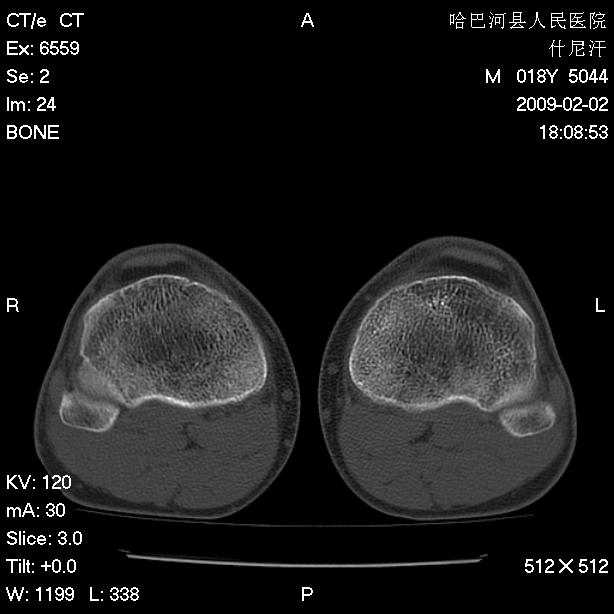

标题: CT17889:外伤后右膝关节反复疼痛3年余 [打印本页]

标题: CT17889:外伤后右膝关节反复疼痛3年余

ct未见明显异常。关节腔未见明显积液,半月板未见明显撕裂。但最好还是mri看看韧带及半月板情况。